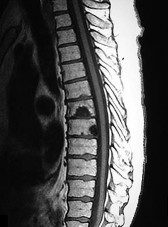

A 65-year-old male presents with classic symptoms of neurogenic claudication. He reports bilateral leg pain and fatigue that worsens with walking but is reliably relieved by leaning forward onto a shopping cart. In the pathogenesis of degenerative lumbar spinal stenosis, which structure is primarily responsible for dynamic central canal compression during spinal extension?

Explanation

In degenerative lumbar spinal stenosis, extension of the spine decreases the sagittal diameter of the canal because the ligamentum flavum buckles inward (shingling), dynamically compressing the thecal sac. Flexion of the spine pulls the ligamentum flavum taut, increasing the available canal space and alleviating neurogenic claudication symptoms. Hypertrophic ligamentum flavum is a major structural contributor to central stenosis.